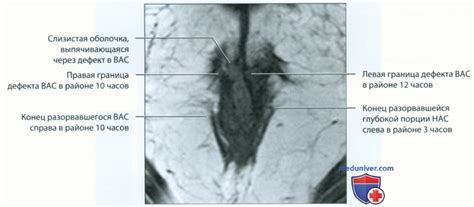

Рентгенограмма, МРТ, УЗИ при недержании кала